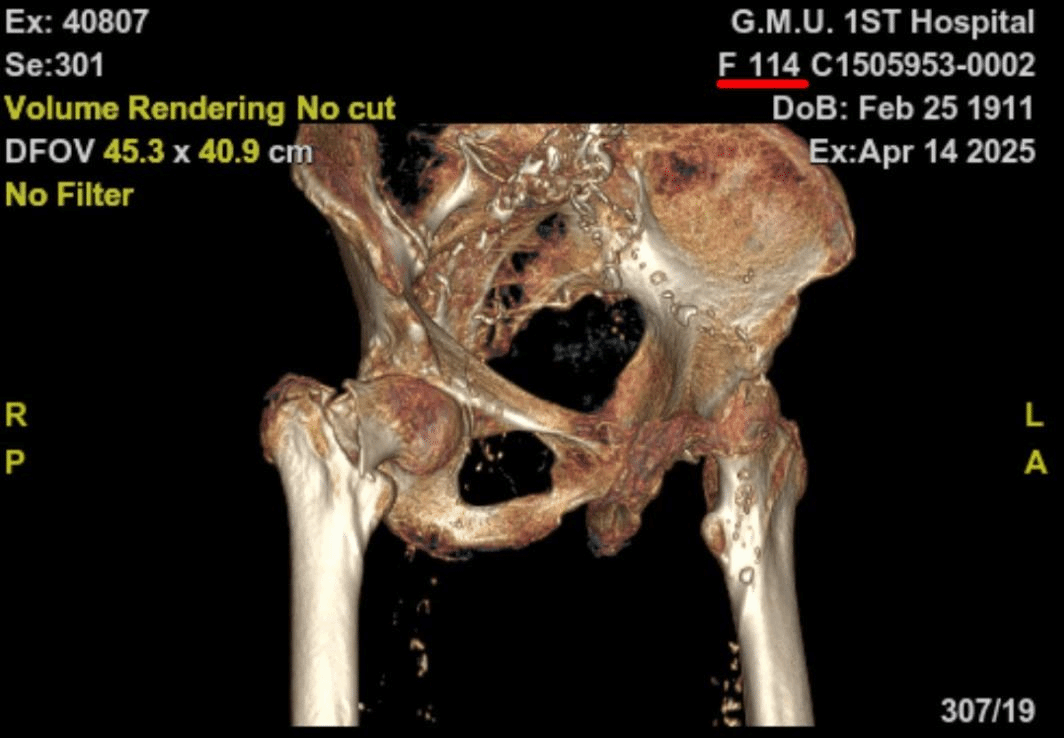

术前全面评估,患者术前有下肢DVT、肺部感染、慢性心功能不全、中度贫血、低蛋白血症,X线片显示股骨皮质极薄、股骨髓腔呈“烟筒样”改变。术前多学科会诊并给予抗凝、控制肺部感染、改善贫血和低蛋白血症、治疗骨质疏松、改善心功能,为麻醉、手术治疗创造条件。

经过精心术前准备,患者各项指标明显改善,考虑到患者骨质疏松非常严重和早期下地活动的要求,经多学科讨论,并且与家属充分沟通和慎重考虑,卢伟杰团队最终决定采用水泥型人工股骨头置换术进行治疗。

术前术后X光照片